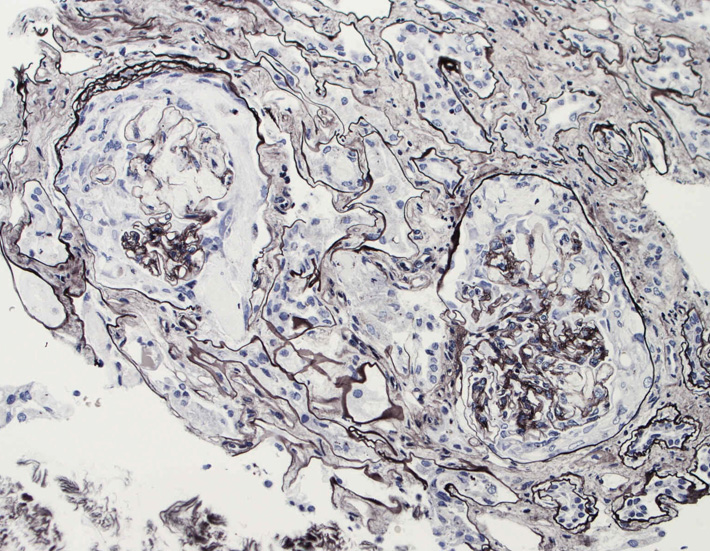

腎臓の病理組織所見-->壊死性糸球体腎炎

Fig.01Fig.02Fig.03

kidney04pas.jpg

kidney05.jpg

kidney06.jpg

Fig.03(PAS)Fig.04(PAM染色)Fig.05(PAM染色)